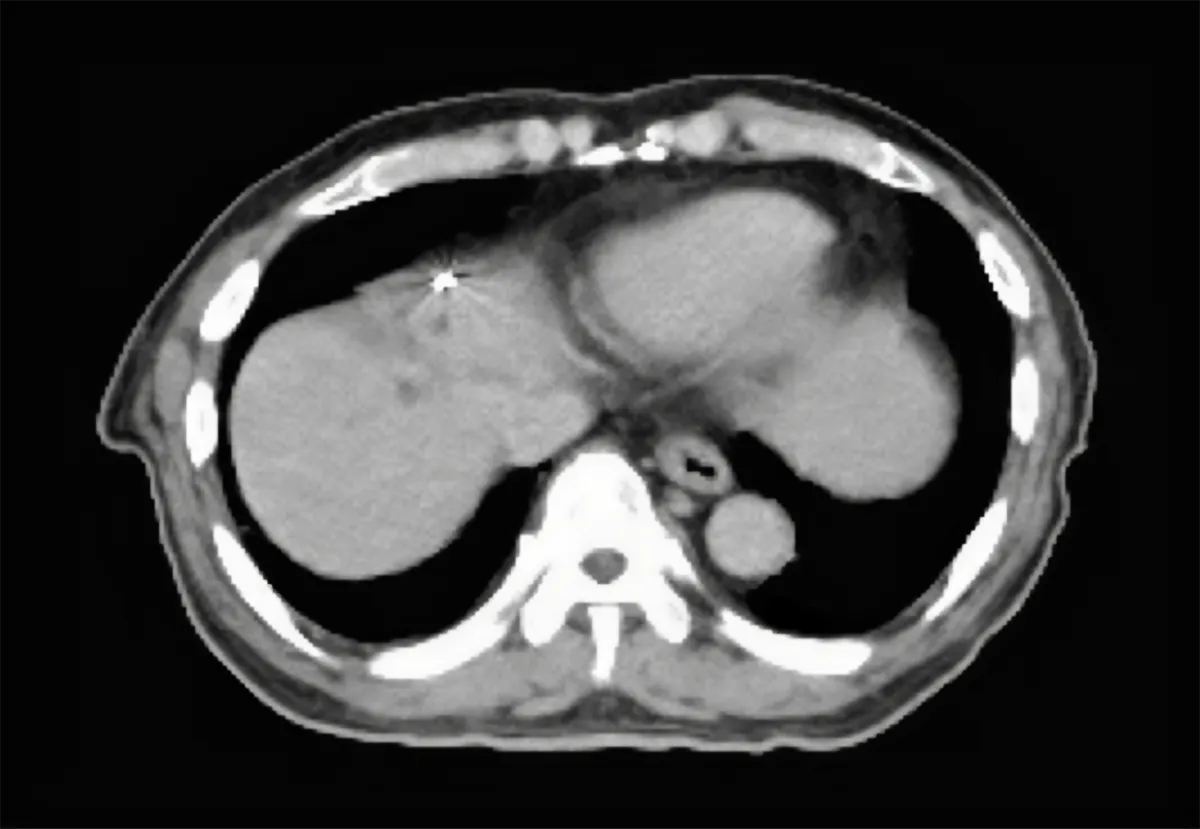

Gold Anchors are typically implanted percutaneously into abdominal organs. This x-ray video shows a 0.28×20 mm marker (GA200-20) implanted in liver while the patient breathes. This example illustrates the value of positioning soft tissue based on a fiducial marker rather than on distant bony anatomy.

X-ray video courtesy of Jun Ishida, MD, PhD, Vice Director, Diagnostic Radiology, Kobe Minimally invasive Cancer Center, Japan.